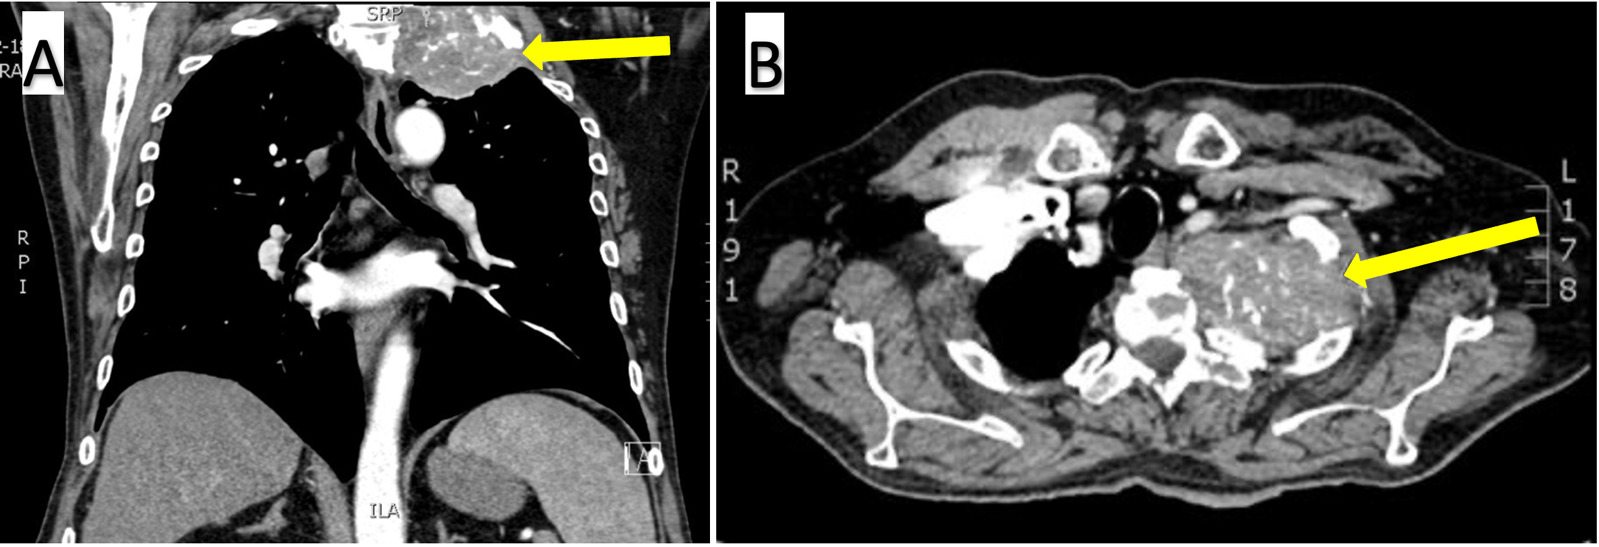

His admission exam confirmed significant atrophy of the left upper extremity and hand and the absence of Horner Syndrome. Basic labs were obtained and were unremarkable. Serum AFP was newly elevated at 16.1 (normal: <8.1). A chest CT with contrast (Figure 1), cervical spine CT, and PET scan revealed a 7.9 x 4.0 x 6.8-centimeter FDG-avid calcified mass with osseous destruction of the left first rib, invasion of the T1 and C7 vertebral bodies, and a nondisplaced pathologic fracture of the T2 transverse process. An interventional radiology-guided biopsy specimen showed poorly differentiated carcinoma containing metaplastic bone spicules (Figure 2A).